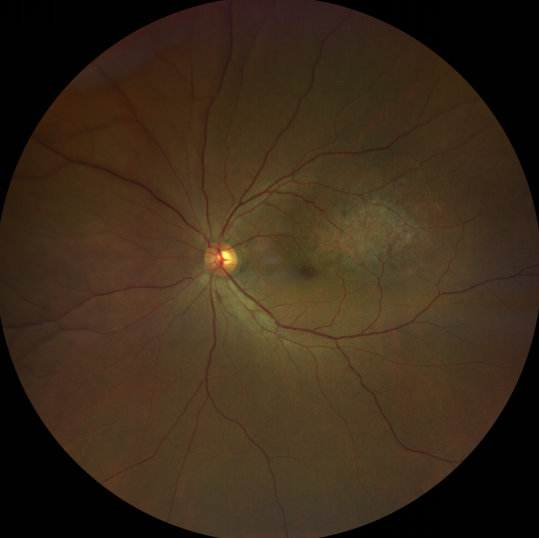

脈絡(luò)膜黑色素瘤患者在發(fā)病早期無眼痛等癥狀,當(dāng)腫瘤較小時(shí)較難發(fā)現(xiàn),隨著病程進(jìn)展,腫瘤增大,發(fā)生滲出性視網(wǎng)膜脫離或累及黃斑,視力下降才就診。

脈絡(luò)膜黑色素瘤惡性程度高,50%的患者會發(fā)生轉(zhuǎn)移,轉(zhuǎn)移到肝、肺等遠(yuǎn)處臟器,常見的轉(zhuǎn)移方式是經(jīng)鞏膜導(dǎo)管擴(kuò)散,經(jīng)視神經(jīng)蔓延者罕見。一旦發(fā)生轉(zhuǎn)移,1年生存率只有10%,即絕大多數(shù)病人在半年至1年間會失去生命。因此,早期診斷和選擇合適的治療方式對有效提高局部腫瘤的控制率、降低腫瘤的遠(yuǎn)處轉(zhuǎn)移率、延長患者的生存率具有重要意義。